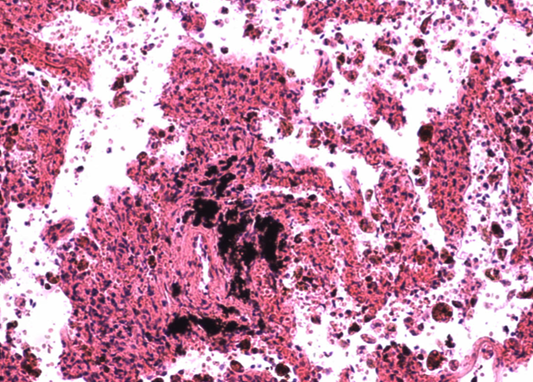

Homo sapiens - Człowiek rozumny - Płuco człowieka z pylicą węglową